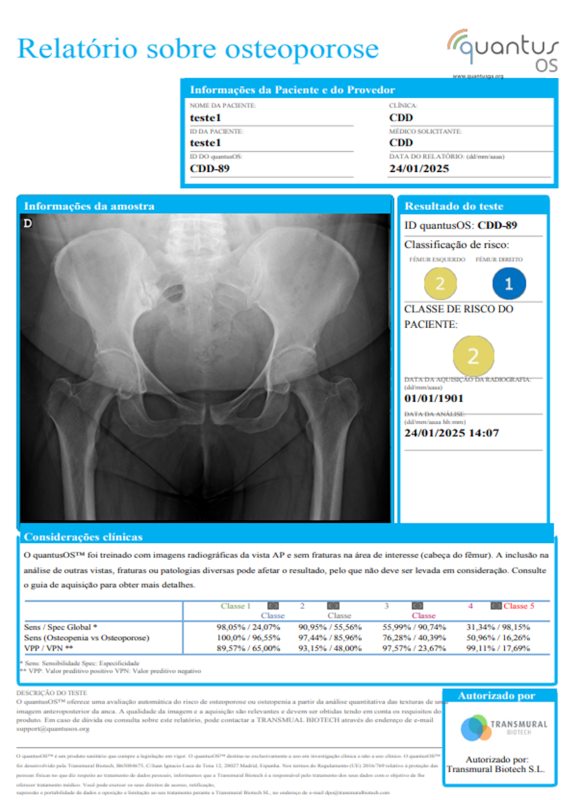

2.1 Os serviços oferecidos pela Transmural (doravante, os "Serviços") consistem em um teste não invasivo, rápido e fácil de usar para a detecção de lesões malignas de osteoporose ou osteopenia com base na análise automática de uma imagem de raio-X AP do quadril fornecida pelo Cliente.

5.1 REGIME GERAL. Os relatórios fornecidos pela Transmural ao Cliente como consequência da prestação dos Serviços indicam uma classificação de risco de que o paciente cujas imagens AP da anca correspondem terá osteoporose ou osteopenia, calculada a partir das informações fornecidas pelo Cliente. Em nenhum caso estes relatórios contêm um diagnóstico com 100% de precisão. Consequentemente, os relatórios fornecidos pela Transmural não devem, em caso algum, ser considerados como o único elemento de diagnóstico para o Cliente tomar decisões médicas. Consequentemente, o Cliente isenta a Transmural de qualquer responsabilidade derivada da tomada de decisões médicas pelo Cliente, pelo pessoal dependente ou pelos pacientes a quem correspondem as imagens fornecidas para a realização dos exames objeto dos Serviços.

5.2 A classificação de risco que a Transmural oferece em seus relatórios pode ser alterada se as imagens de raios-X fornecidas pelo Cliente não cumprirem rigorosamente as condições estabelecidas no referido "Guia de Aquisição de Imagens", que também está disponível na Plataforma.

1. Os relatórios fornecidos pela Transmural ao Usuário em decorrência da prestação dos Serviços indicam uma classificação de risco de malignidade de osteoporosis ou osteopenia correspondente às imagens AP do quadril previamente fornecidas pelo Usuário. Em nenhum caso esses relatórios contêm um diagnóstico com 100% de certeza. Consequentemente, os relatórios fornecidos pela Transmural não devem, em caso algum, ser considerados como um único elemento diagnóstico para a tomada de decisão médica do Usuário. Consequentemente, o Usuário isenta a Transmural de toda responsabilidade derivada da tomada de decisão médica por parte do mesmo, ou de terceiros sob sua responsabilidade, ou ainda dos pacientes a quem correspondam as imagens fornecidas para a realização dos testes objeto dos Serviços.

2. A classificação de risco que a Transmural oferece nos seus relatórios depende, entre outros fatores, da qualidade das imagens disponibilizadas pelo Usuário, nos termos indicados no "Guia de Captação de Imagens" já referida e disponível na Plataforma. Portanto, essas classificaçãos podem ser alterados caso as imagens do quadril fornecidas pelo Usuário não atendam estritamente às condições estabelecidas no "Guia de Captação de Imagens".